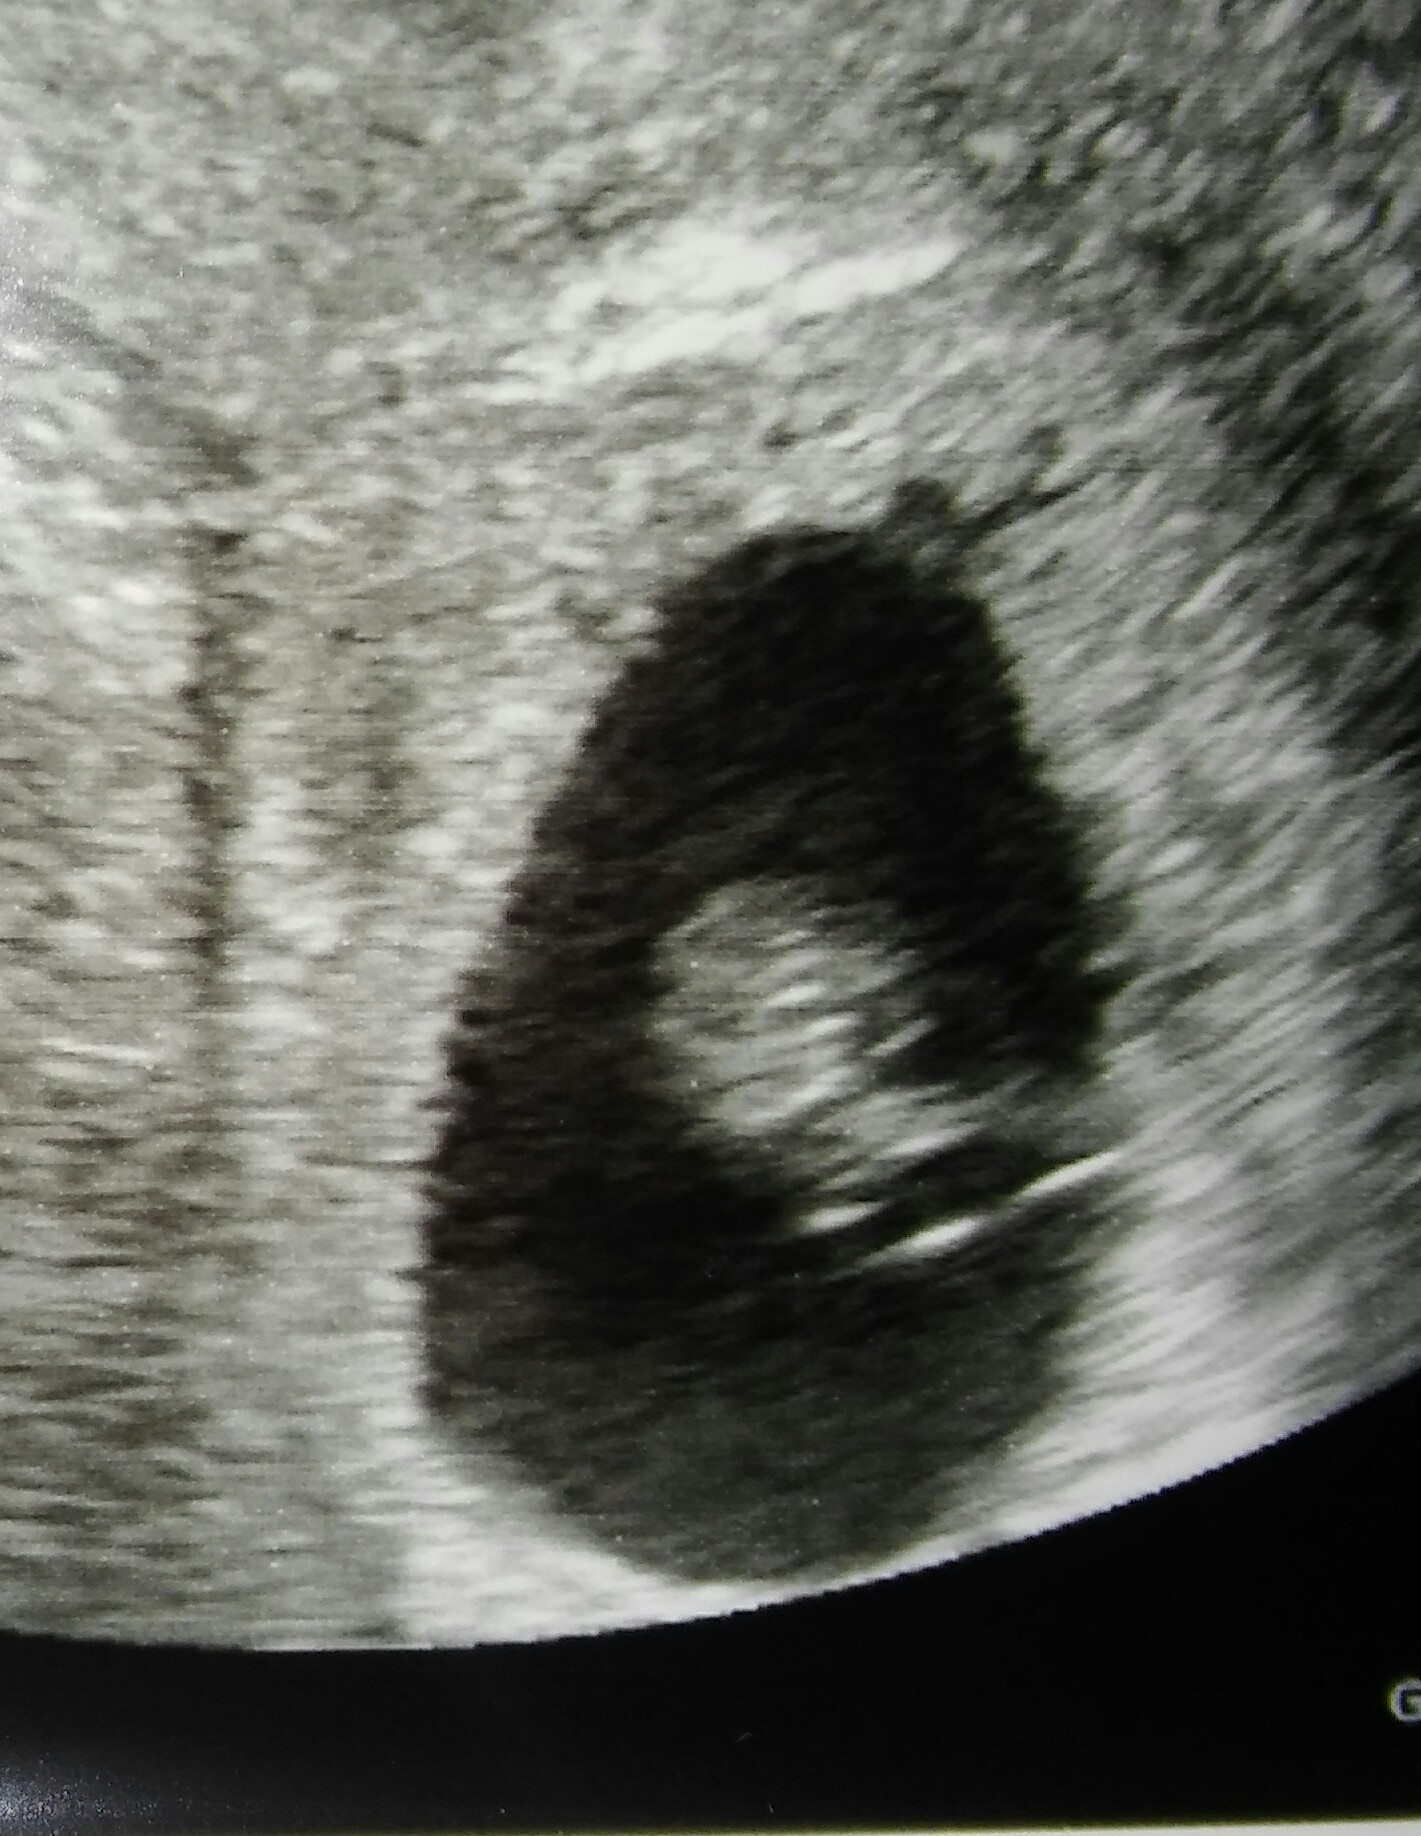

Hej dziewczyny :) chwilę mnie nie było.. Czuję się jak bym się zdarzyła z tirem.. Mdłości, bekanie, zgaga, zmęczenie, senność, tkliwe piersi, itd itd... :) dziś robiłam betę i wynik 36 655, w czwartek kolejne usg, mam nadzieję zobaczyć maluszka, bo w tamtym tygodniu był tylko pęcherzyk :) muszę jeszcze sporo nadrobić, ale wyłapałam wiadomość o bliźniakach :) gratulacje!

Byłam dziś wreszcie u lekarza po ogromnych perypetiach, całkiem innego ale po nieudanej pierwszej wizycie o czternastej musiałam stanąć na głowie żeby mieć dzisiaj te usg. Jest pęcherzyk jest ciałko żółte! Mąż był przy usg , Myślałem że trzeba będzie go reanimować, niech ciekawe co to będzie dalej. Dostałam duphaston dwa razy dziennie i od razu L 4